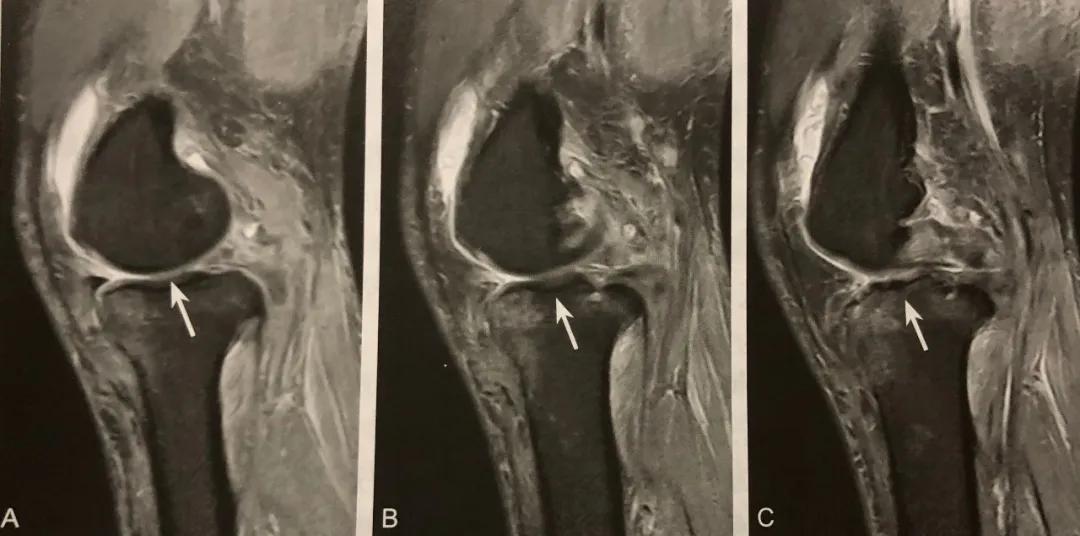

领结消失征

A~C.T2WI矢状位,内侧半月板体部明显变小,连续三个层面正常“领结”样形态部分缺如,呈“领结消失”征,胫骨平台见骨髓水肿

正常半月板在 MRI 矢状位呈领结样表现,领结消失征代表至少两个不同层面 MRI 矢状位领结影消失,提示半月板损伤。

阅片要点:

1. 半月板桶柄样撕裂的影像学表现;

2. 在 MRI 矢状位观察;

3. 至少两个不同层面 MRI 矢状位领结影消失,特异性较高;

4. 当领结消失征和其他碎片移位征象联合时,特异性明显提高。